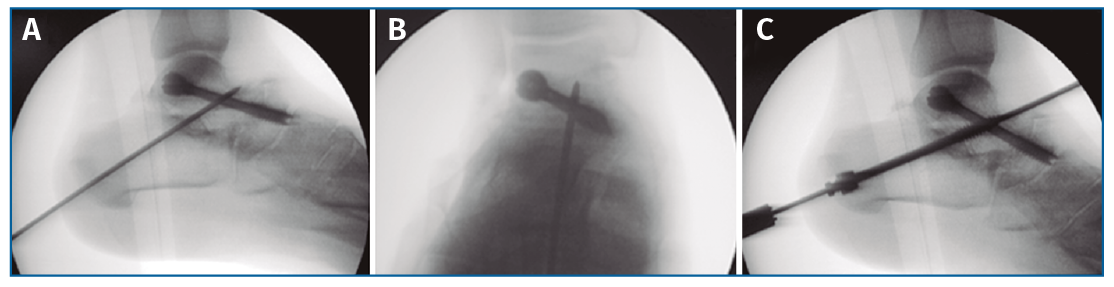

Finalmente, se realiza la osteosíntesis a compresión con un tornillo (ICOS® 6,5 mm; un caso con tornillo HCS® Synthes 6,5) primero de la TN (Figura 3) y después de la ST (Figura 4)(29)(30).

Figura 4. Fijación con aguja guía de la articulación subastragalina bajo control fluoroscópico en lateral (A) y anteroposterior (B) y osteosíntesis a compresión con un tornillo (C; ICOS® 6,5 mm).